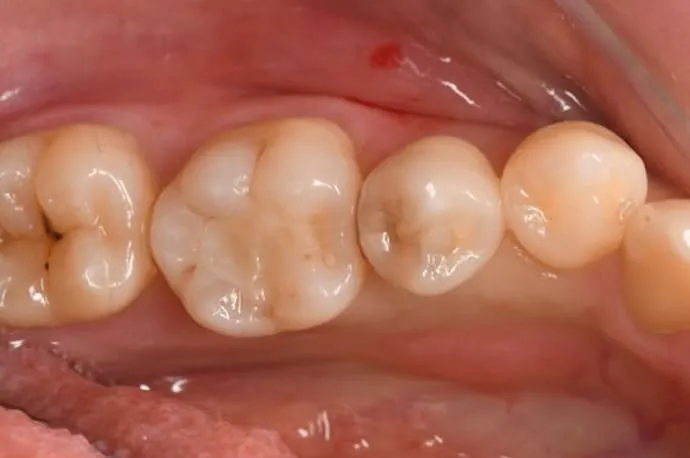

大きい虫歯:被せ物(クラウン)・抜髄有無

| 治療回数 | 根管治療なしの場合2回(根管治療が必要な場合は、必要に応じ1~3回追加) |

| 術後の痛み | 被せ物が必要な深い虫歯では、冷たい物でしみたり、噛むと痛みが出ることがあります。型採りから完成まで仮の蓋で過ごすため、噛み合わせや外れによる痛みが出ることがあります。術後の痛みが強い場合や、長く続く場合は、追加の治療が必要になることがあります。 |

虫歯を除去した後、残っている歯の量が少ない場合は、部分的な詰め物では歯が割れる可能性があります。その場合は、歯全体を覆う被せ物(クラウン)を使用することで、長期的に安定した状態を保つことができます。材質は保険診療・自費診療の中から選択可能で、患者さまのお口の状態に合わせた適切な材料を提案します。